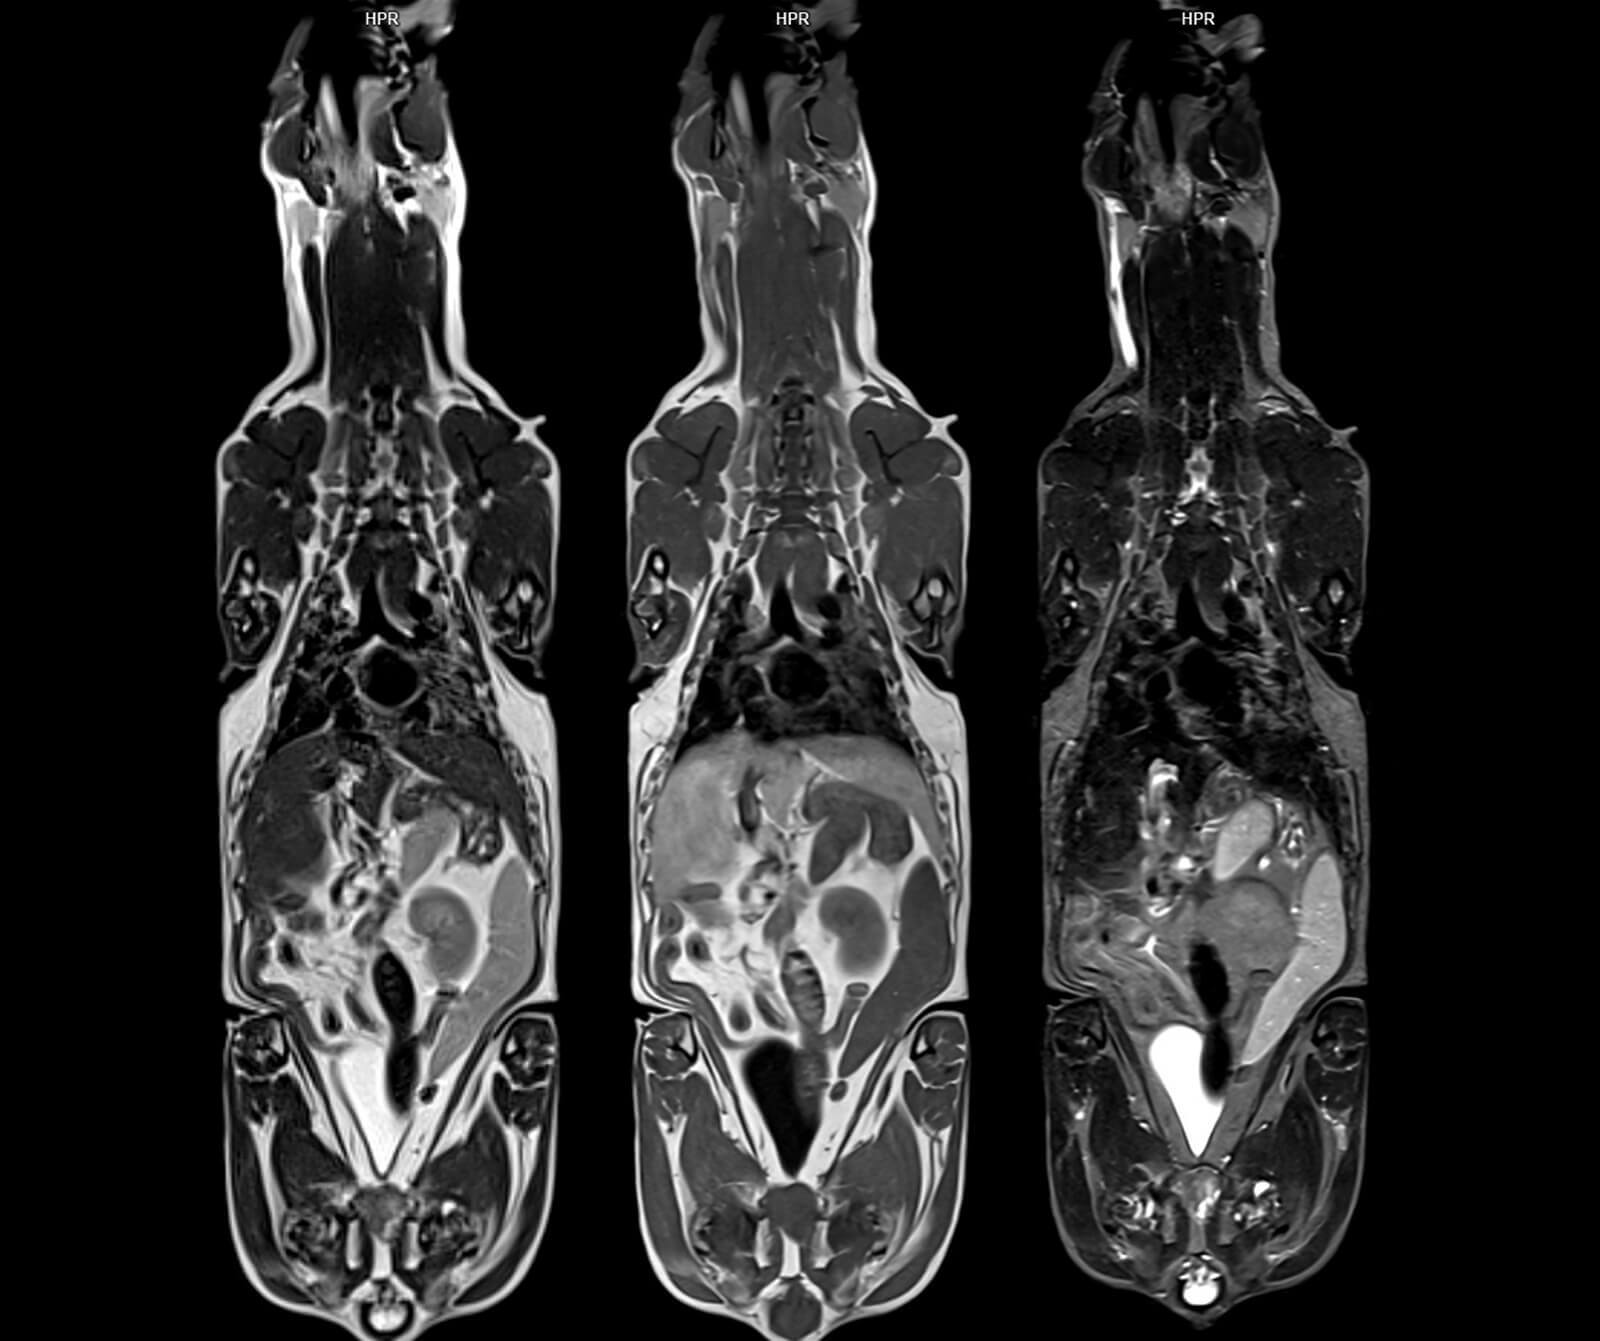

Veteriner hekimliğinde MR; beyin, omurilik, sinir sistemi, kas-iskelet sistemi ve iç organ hastalıklarının değerlendirilmesinde kritik rol oynar. Kemik yapılar dâhil olmak üzere vücudun tüm bölgeleri MR ile ayrıntılı şekilde incelenebilir.

• Göğüs ve karın içi organ hastalıkları

• Yumuşak doku ve organ tümörleri

• Kanser evrelemesi ve tedaviye yanıtın takibi

• Özellikle beyin, karaciğer, pankreas, meme ve prostat tümörleri